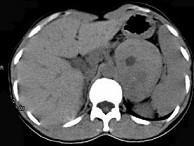

问题 女,36岁,无任何症状,体检时超声发现左侧肾上腺区占位,CT扫描如图所示,应诊断为()

选项 A.左肾上腺腺瘤 B.左肾上腺囊肿 C.左肾上腺嗜铬细胞瘤 D.左肾上腺髓样脂肪瘤 E.左肾上腺转移瘤

答案 A